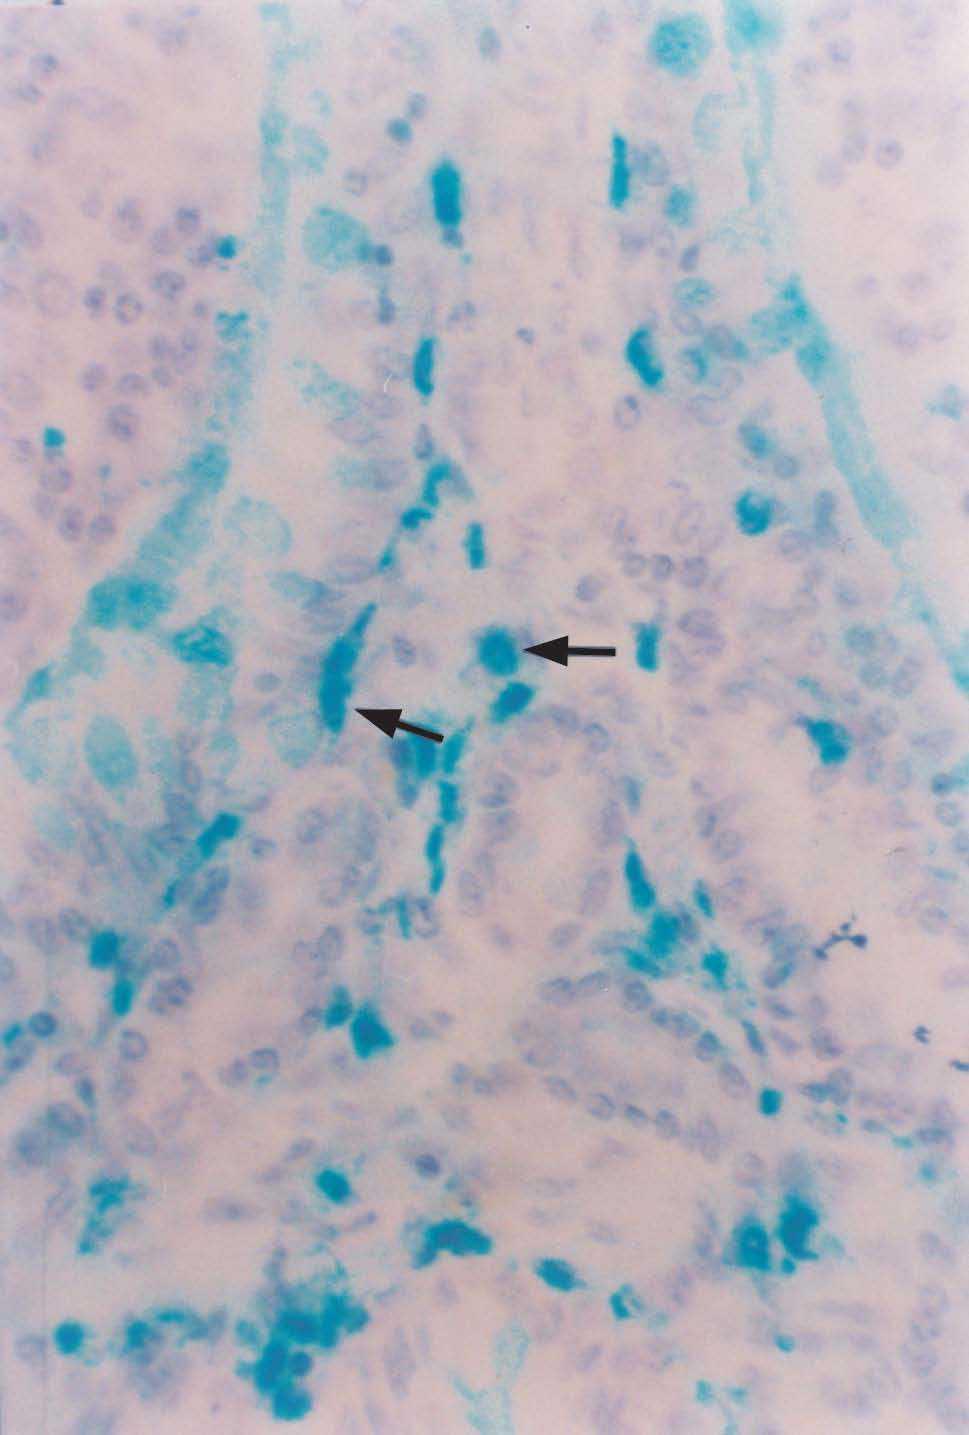

In both groups the histological study revealed lymphoid structures called appendicular patches, protruding towards the lumen. These plaques were located at mucosal and submucosal level, and were separated by crypts and tubular glands with the presence of enterocytes, enteroendocrine cells and goblet cells. The plaques were in turn lined by a simple cylindrical epithelium with basal nuclei and a pale cytoplasm, and including M cells, macrophages and lymphocytes, among other cell types. Beneath the epithelium, at plaque level, the macrophages were seen in different regions: follicular, interfollicular, subdomal, and in the lamina propria (VIM) reflecting their presence in areas that induce and execute local immune responses. In addition, an increased presence of mast cells was noted in the chorion of the villi in sensitized animals (fig. 2).

Figure 2.--Alcian blue-positive mast cells in the villous chorion of the cecal appendix. Rabbit belonging to group 2 (G2, sensitized) (x 450).